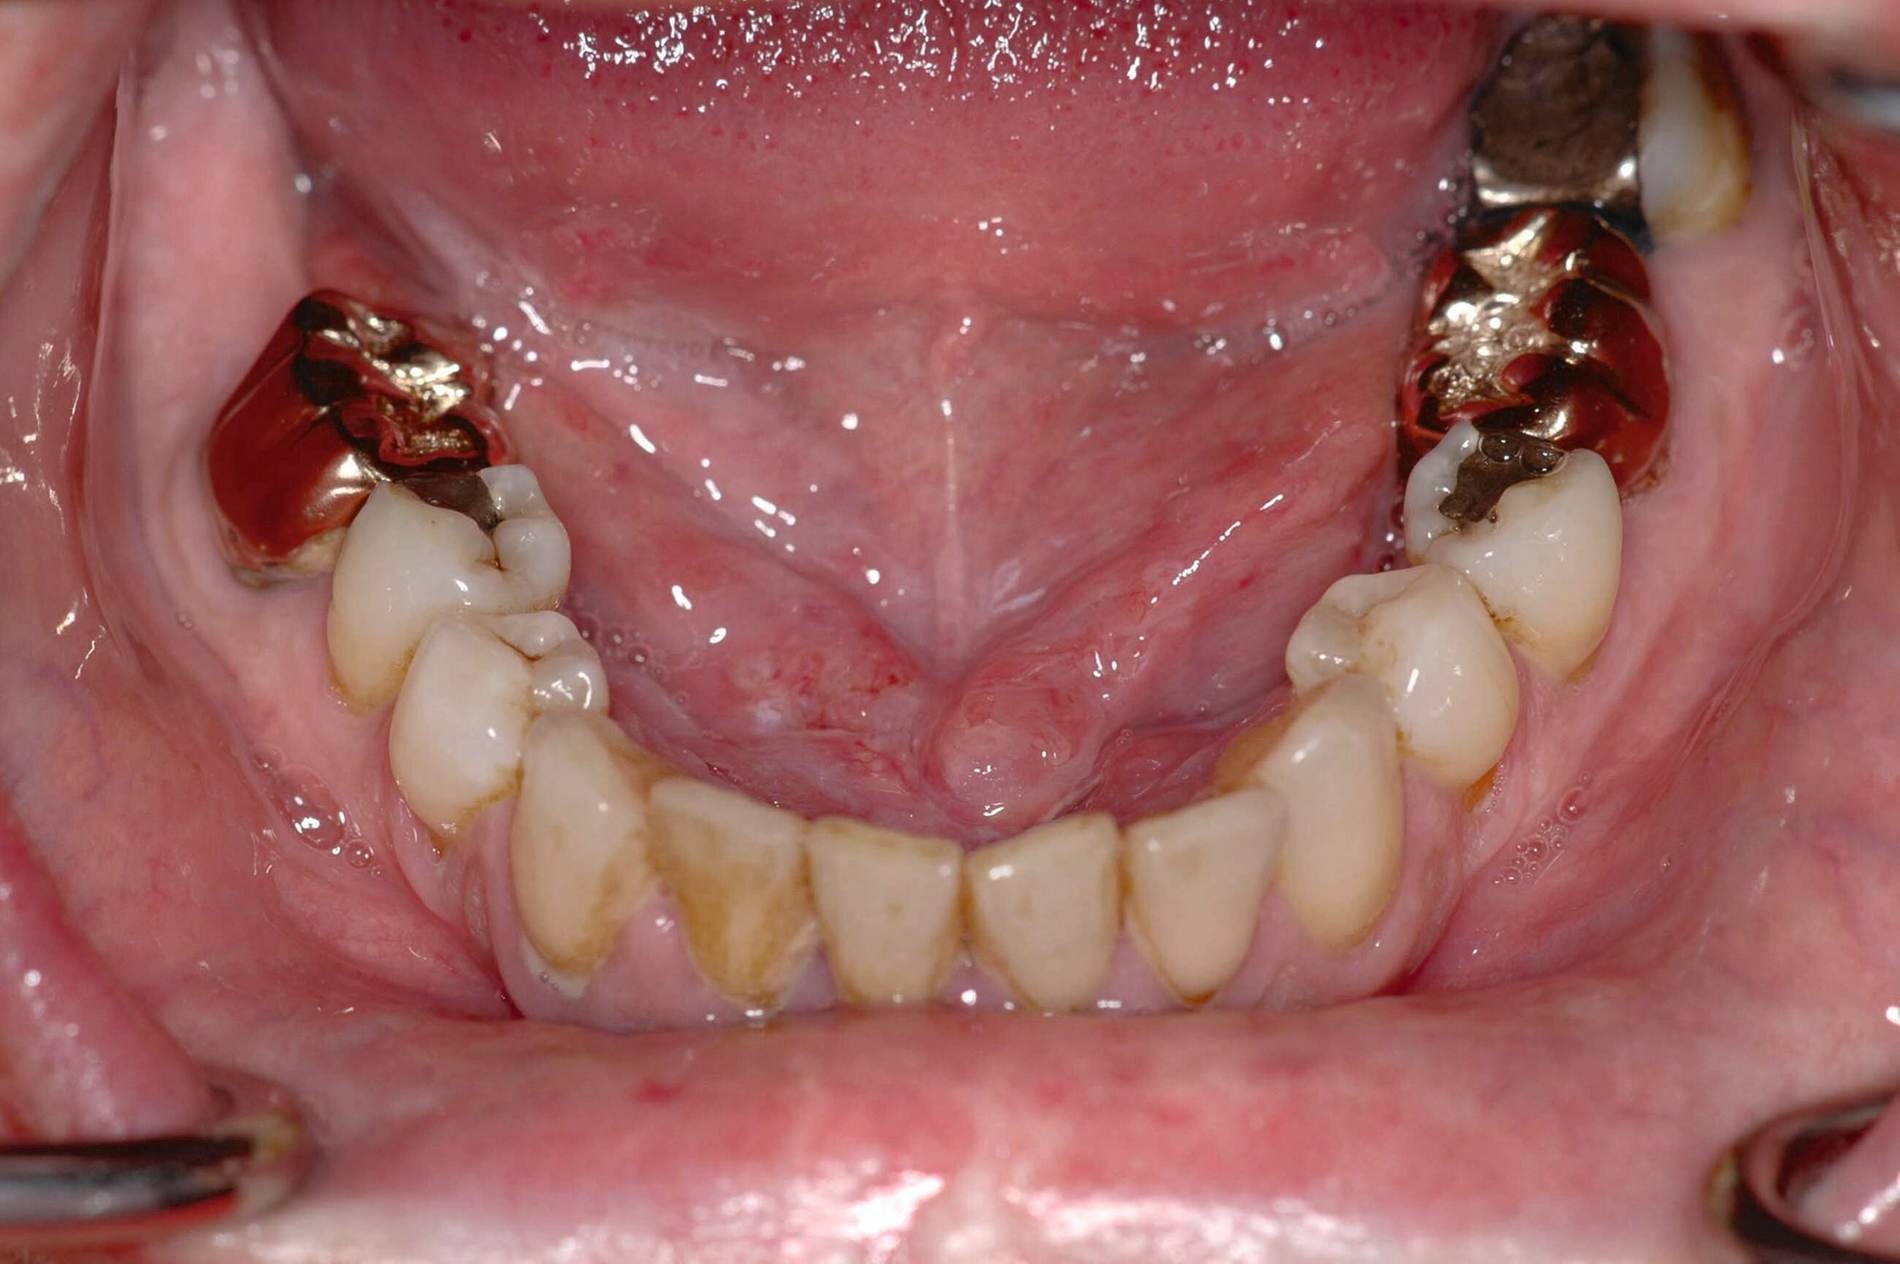

Das Problem: Die geschätzte Zahl der Neuerkrankungen bei Tumoren der Mundhöhle und des Rachenraums lag – nach den aktuellsten Zahlen des Robert-Koch-Instituts (RKI) – im Jahr 2018 bei über 14.000 Fällen deutschlandweit. Davon waren 9.820 Männer und 4.490 Frauen betroffen. Gemessen an der Zahl aller Krebserkrankungen waren dies bei Männern 3,7 Prozent – Tumoren der Mundhöhle nehmen damit bei den Neuerkrankungen die achte Position bei den Männern ein. Bei den Frauen war es mit 1,9 Prozent die 13. Stelle. Die Fünf-Jahres-Überlebensrate in Deutschland lag bei Männern bei nur 52, bei Frauen bei nur 62 Prozent.

Die Relevanz des Projekts liegt nach Angaben der Forschenden auf der Hand: Obwohl sich die Behandlungsstandards in Diagnostik und Therapie in den vergangenen Jahrzehnten kontinuierlich verbessert hätten, habe sich dies nicht merklich positiv auf die Absenkung der Mortalitätsrate ausgewirkt. Als Grund geben die Forschenden an, dass sich mehr als die Hälfte der Betroffenen erst in einem fortgeschrittenen Stadium an einen Zahnarzt, einen Mund-, Kiefer- und Gesichtschirurgen oder eine ärztliche Fachdisziplin (zum Beispiel Hals-Nasen-Ohren-Heilkunde) wenden.

Das liege unter anderem daran, dass die Erkrankung für Betroffene relativ lange schmerzlos und asymptomatisch verlaufe. Zusätzlich sei bei den Patientinnen und Patienten ein sehr hohes Verdrängungspotenzial gegenüber der Erkrankung selbst zu beobachten. Dem geschuldet folge nach der Diagnose zumeist eine sehr aufwendige Therapie, erläutern die Forschenden. Das Resultat seien oft bleibende, funktionelle Einschränkungen und auch sichtbare Defekte.